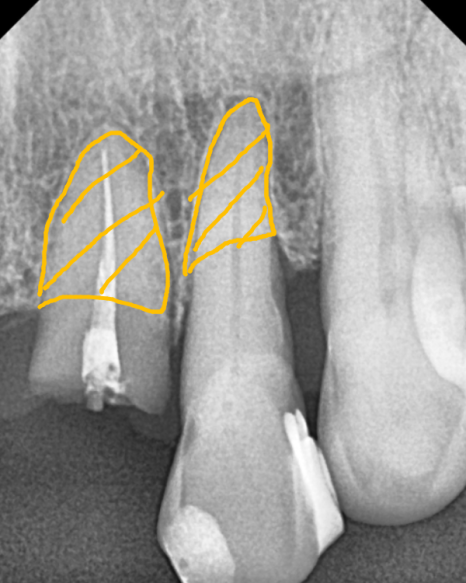

여러 각도로 살펴본 결과,

가장 안정적으로 버틸 수 있겠다는

위치를 기준으로 계획을 잡았습니다.

250221

이 기준을 바탕으로

양쪽 끝 위치에만

임플란트를 식립하고

가운데는 보철(브릿지)로 연결하는 방식으로

치료를 진행했습니다.

임플란트 뿌리가 예상했던 위치에

큰 변수 없이 잘 들어간 것을

확인할 수 있었습니다. ^^